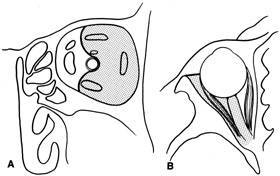

Lateral orbitotomy provides excellent access to deep lesions in the subperiosteal, peripheral, or intraconal space lateral to the optic nerve (Fig. 8A, B).

Fig. 8. Coronal (A) and axial (B) views in an illustration of areas (shaded) amenable to lateral orbitotomy.

Although intraconal lesions medial to the nerve sometimes can be approached laterally, great care to identify and protect the optic nerve is required during deep orbital dissection. Because the eyelid crease incision allows such wide exposure of the superolateral orbit, it is often possible to remove fairly large orbital lesions without removing the lateral orbital wall (Fig. 9). Surgery in this case proceeds as described to exposure of the superior and lateral bony orbital rims. It is not necessary to reflect periosteum over the external surface of the rim. Instead, once periosteum at the rim is exposed, it is cut with cautery and then only the mesial periorbita need be elevated internally to expose orbital contents with subsequent intra-orbital dissection carried out with the lateral rim in place. Often it is preferable to initially attempt to remove intraconal or lacrimal fossa lesions in this fashion. If exposure proves inadequate, the periosteum over the external surface of the lateral orbital rim can be elevated and osteotomies and removal of the lateral wall still can be carried out.